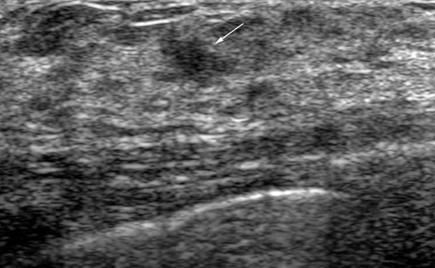

The target dataset was developed from 35 breast ultrasound scans that were segmented by an image-processing expert with extensive experience in breast lesion segmentation (the second author). The images, collected from the Web, are of different dimensions, ranging from to pixels (Figure 3, images resized for sake of illustration). These are the same images used to introduce EFIS originally [1].

Ultrasound images are generally difficult to segment, primarily due to the presence of speckle noise and low level of local contrast. It should be noted that the segmentation of ultrasound actually does require a complete processing chain, (including proper preprocessing and post-processing steps). However, the purpose of using these images was solely to demonstrate that the accuracy of the segmentation can be increased with the application of SC-EFIS.